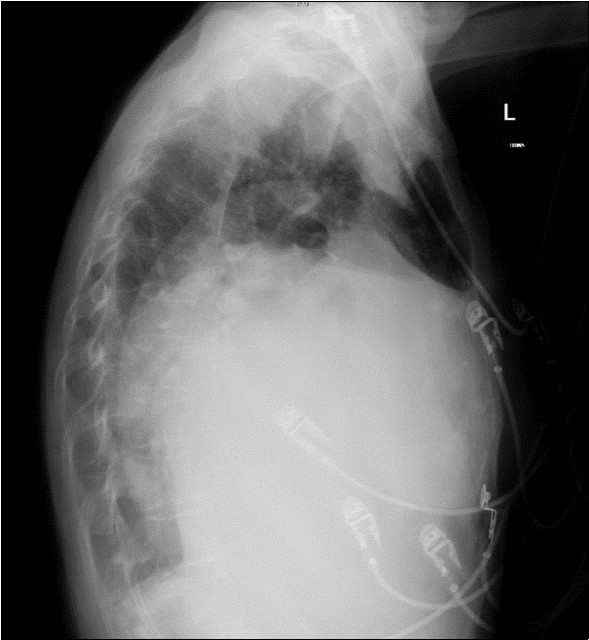

A 64-year-old woman was admitted to the Intensive Care Unit (ICU) after a medical emergency team (MET) call from the cardiology ward due to a reduced level of consciousness and respiratory distress. Past medical history included rheumatic fever as a child and chronic atrial fibrillation. She had been admitted to hospital 3 days previously with worsening shortness of breath. On observation she was drowsy but rousable to voice, with a respiratory rate of thirty breaths per minute. Examination revealed a raised jugular venous pressure, a pan-systolic murmur as well as a long mid-diastolic murmur, both loudest at the apex and radiating to the axilla, a soft first heart sound, a displaced tapping apex beat, and bi-basal medium-intensity inspiratory crepitations. Her electrocardiogram showed atrial fibrillation with a rapid ventricular response of 126 beats per minute. Her arterial blood gas demonstrated an acute on chronic respiratory acidosis with a pH 7.02, PaCO2 176 mmHg, and a HCO3- of 43 mmol/L. An antero-posterior (AP) chest x-ray on admission displayed cardiomegaly, splayed carina and hilar venous congestion, with a lateral film showing the left atrium occupying a significant part of the chest cavity (see Figure 1a, Figure 1b).

Figure 1b.Chest X-ray Lateral view. Findings showing enlarged left atrium occupying large amounts of the thoracic cavity, both horizontally and vertically

Chest X-ray Lateral view. Findings showing                  enlarged left atrium occupying large amounts of the thoracic cavity, both horizontally and vertically